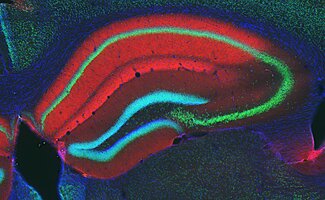

GABA Receptors

GABA receptors respond to the brain’s major inhibitory neurotransmitter GABA.

Glutamate Receptors

Glutamate receptors are the most abundant type of excitatory neurotransmitter receptors in the mammalian CNS.